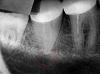

olegb Опубликовано 21 ноября, 2007 Автор Поделиться Опубликовано 21 ноября, 2007 +1 Сложно пройти каналы . Хотя попробовать можноВ реале Мне тоже так сказали. На 3-ем снимке видно что канал справа кривой и не запломбирован, скорее всего он и стал причиной образования гранулемы... Мне 20 лет, никакими хроническими заболеваниями не страдаю. Удалять зуб и ставить имплант не хотелось бы из-за молодого возраста и недолговечности имплантов. Но похоже что всё-таки придётся удалять, но ставить мост я не хочу дабы не портить и продлить жизнь 6 и 8 зубам. Если всё таки придется удалять, помогите пож-ста с общими наставлениями(какой анастетик выбрать, как вести себя после удаления) Ссылка на комментарий

Svarog Опубликовано 22 ноября, 2007 Поделиться Опубликовано 22 ноября, 2007 (изменено) Считаю,что напросно расстались с зубом!!!снимки конечно не ахти какие,но побороться следовало бы.а вы сдались без боя.ваш семейный стоматолог судя по всему и лечил этот зуб.наверное старинным советским методом при помощи резорцин-формалина.если это так,то мой совет подыскать другого доктора.кстати совет еще один.обратите внимание на шестой зуб.фиброзный периодонтит налицо в хронической форме.а то не дай бог заболит и с ним растанетесь Изменено 22 ноября, 2007 пользователем dr.Mengele Ссылка на комментарий